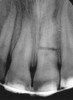

Figure 2a  Another case that clearly shows additional canal anatomy (distolingual root) not easily detected by periapical radiographs. Periapical radiograph depicting possible widened periodontal ligament (A). The CBCT clearly shows the missed canal in all three dimensions (B). The postoperative periapical radiograph shows the re-treatment, which includes the obturation of the distolingual canal24 (C).

Figure 2a

Figure 2b  Another case that clearly shows additional canal anatomy (distolingual root) not easily detected by periapical radiographs. Periapical radiograph depicting possible widened periodontal ligament (A). The CBCT clearly shows the missed canal in all three dimensions (B). The postoperative periapical radiograph shows the re-treatment, which includes the obturation of the distolingual canal24 (C).

Figure 2b

Figure 2c  Another case that clearly shows additional canal anatomy (distolingual root) not easily detected by periapical radiographs. Periapical radiograph depicting possible widened periodontal ligament (A). The CBCT clearly shows the missed canal in all three dimensions (B). The postoperative periapical radiograph shows the re-treatment, which includes the obturation of the distolingual canal24 (C).

Figure 2c

Initially, case studies appeared in the endodontic literature in which patients underwent CBCT imaging for the purposes of diagnosis20-22 and presurgical treatment planning.19 Recent reports have successfully shown the use of CBCT to locate missed canals,23 detect the extent of dentoalveolar fractures,20 identify resorption patterns,22 and compare cystic with granulomatous periapical lesions.17 Figure 2A through Figure 2C show a case in which the missed canal was suggested by periapical radiographs but confirmed with CBCT.24 Similarly in Figure 3A through Figure 3D, the additional diagnostic information attained from CBCT confirmed the diagnosis and extent of the root fracture, which initially was observed in the periapical radiographs (Figure 4A and Figure 4B).20 Notably, the extent of the lingual fracture as well as any alveolar complications could be visualized by CBCT only.